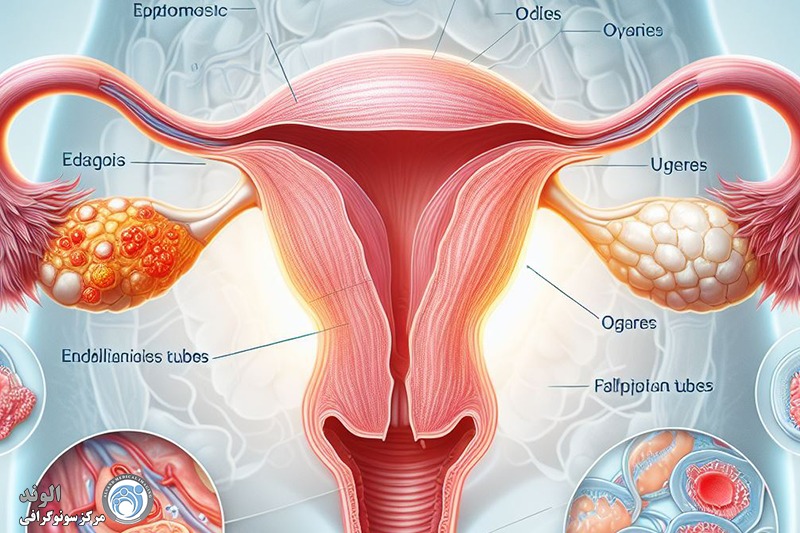

اندومتریوز؛ آندومتر بافتی است که داخل رحم را می پوشاند. اندومتریوز وضعیتی است که در آن بافتی مشابه به بافت آندومتر در خارج از قسمت رحم یافت می شود. در ناحیه لگن و شکم تحتانی (شکم) و به ندرت در سایر نواحی بدن «به دام افتاده» است. در حال حاضر مشخص نیست که چه چیزی باعث آندومتریوز می شود. عوامل متعددی وجود دارد که احتمالاً دلایل ژنتیکی، ایمونولوژیکی و هورمونی را شامل می شود.

این بیماری زمانی اتفاق میافتد که بافت مشابه با بافت داخلی رحم (آندومتر) در جایی خارج از رحم رشد میکند، معمولاً در تخمدانها، لولههای فالوپ یا سایر اندامهای لگنی. علائم آندومتریوز میتواند شامل دردهای شدید قاعدگی، درد در حین رابطه جنسی، مشکلات باروری و خونریزی غیر طبیعی باشد. با این حال، بسیاری از زنان مبتلا به آندومتریوز ممکن است بدون علائم جدی یا فقط علائم خفیف داشته باشند، که این ممکن است تشخیص بیماری را دشوار کند.

اندومتریوز یک بیماری زنان است که در آن بافتی مشابه به بافت داخلی رحم (اندومتر) در خارج از رحم رشد میکند. این بیماری میتواند به شدت دردناک باشد و مشکلاتی چون ناباروری، دردهای مزمن لگنی، و اختلالات قاعدگی را ایجاد کند. تشخیص زودهنگام اندومتریوز اهمیت زیادی دارد زیرا میتواند به مدیریت مؤثرتر علائم و بهبود کیفیت زندگی بیماران کمک کند. یکی از روشهای رایج و غیرتهاجمی برای تشخیص اندومتریوز استفاده از سونوگرافی است که به ویژه در شناسایی برخی از ویژگیهای این بیماری بسیار مؤثر است.